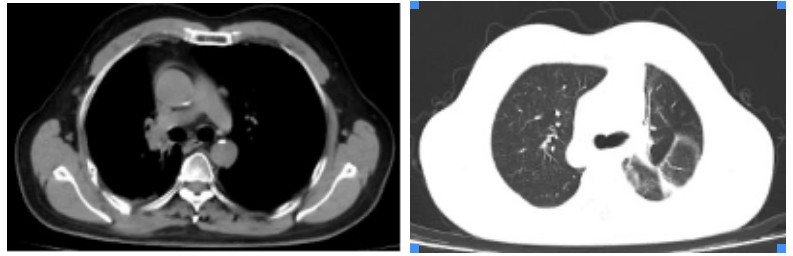

Figure 4. Three years after carbon ion therapy for chest tumor